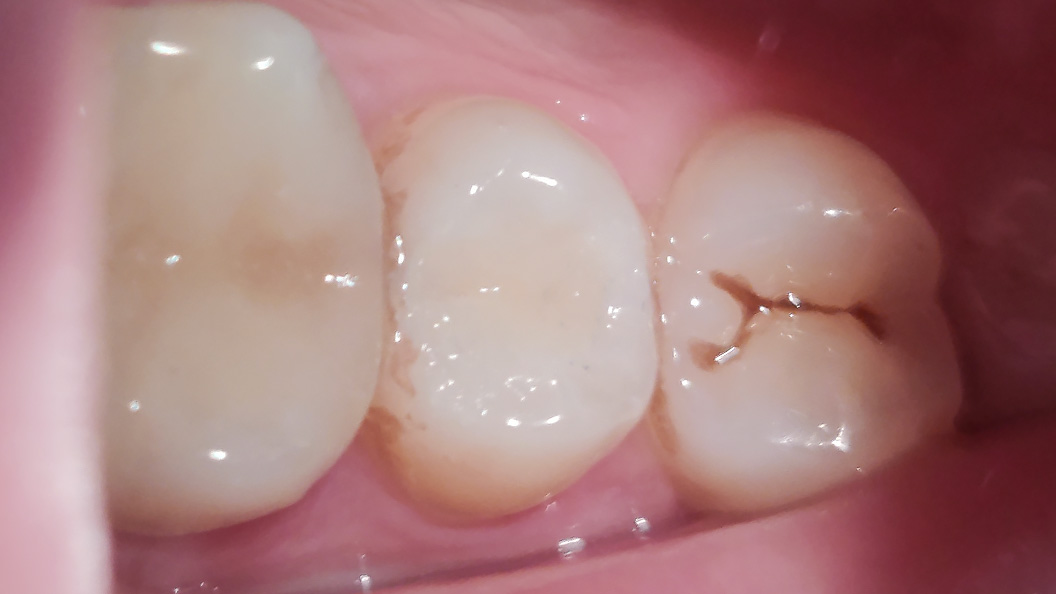

До и после лечения

Пациент обратился с жалобами на эстетический недостаток в области правого верхнего зуба. После обработки полости под контролем кариес-маркера была обнаружена полость средней глубины. Дно и стенки плотные, гладкие, при зондировании крепетируют. Реакция не перкуссию и холодную пробу отрицательная. Диагноз — хронический средний кариес.

При среднем кариесе кариозная полость находится в пределах эмали и среднего слоя дентина. Если его не лечить, он может стать глубоким. В хронической форме пациент может обратиться к врачу слишком поздно, потому что нет такой интенсивности болевых ощущений, как при острой форме.